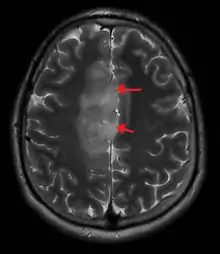

An X-ray computed tomography (CT) or magnetic resonance imaging (MRI) scan is necessary to characterize the anatomy of this tumor as to size, location, and its heter/homogeneity. However, final diagnosis of this tumor, like most tumors, relies on histopathologic examination (biopsy examination).

If resected, the surgeon will remove as much of this tumor as possible, without disturbing eloquent regions of the brain (speech/motor cortex) and other critical brain structure. Thereafter, treatment may include chemotherapy and radiation therapy of doses and types ranging based upon the patient's needs. Subsequent MRI examination are often necessary to monitor the resection cavity.